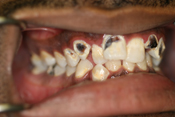

WORST TEETH Pictures from Warren Dentistry

This can happen to your teeth when proper Dental Hygiene is not practiced.

Patient 1